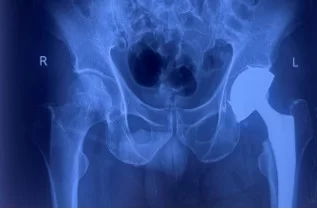

Phẫu thuật thay khớp háng bán phần hay tạo hình đầu gần xương đùi một phần là thủ thuật chỉnh hình dùng để điều trị cho một số trường hợp gãy cổ xương đùi. Trong đó, chỏm xương đùi sẽ được cắt bỏ và thay thế bằng các bộ phận có chất liệu như: kim loại, titanium, nhôm, cobalt hoặc nhựa rất cứng…

Phương pháp phẫu thuật này thường được chỉ định cho những trường hợp gãy cổ xương đùi di lệch nhiều trên bệnh nhân cao tuổi hoặc người không đảm bảo sức khỏe để thực hiện các ca mổ dài và phức tạp

Bên cạnh đó, một trong những trường hợp phổ biến được bác sĩ chỉ định thay khớp háng bán phần chính là gãy cổ xương đùi. Tình trạng này rất thường xảy ra ở người Việt. Trong đó, 80% ca thay khớp háng bán phần là do gãy cổ xương đùi ở người lớn tuổi.

– Đừng quên tái khám định kỳ với bác sĩ phẫu thuật chỉnh hình để thăm khám và chụp X-quang nhằm theo dõi thường xuyên, ngay cả khi khớp háng có vẻ đang hoạt động tốt.